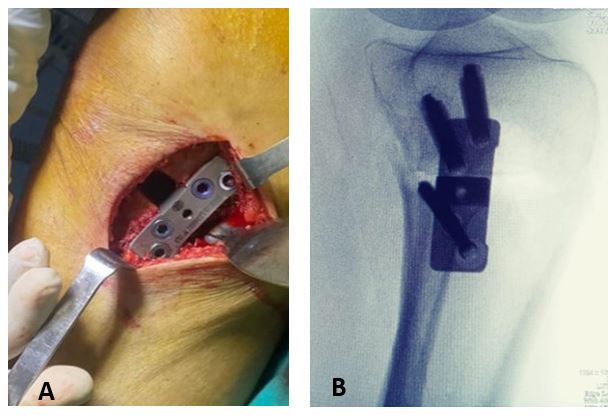

Mediante una incisión oblicua en cara anteromedial de la pierna se expuso la cara medial del tercio proximal de la tibia y liberación del ligamento colateral medial. Posteriormente, bajo visión directa con el intensificador de imágenes, se colocó una clavija desde medial, con dirección al tercio superior de la articulación tibioperonea proximal para marcar la localización del corte de la osteotomía (Fig. 2). Se realizó luego una osteotomía incompleta, que en el plano sagital debe ser paralela al slope tibial y sin afectar la cortical lateral de la tibia. Se inició el corte con sierra oscilante y se finalizó mediante escoplos. Luego de esta última, se procedió a su apertura gradual (Fig. 3). Una vez lograda la corrección planificada, se colocó una placa tipo Puddu, con los dos tornillos proximales para esponjosa, de 6.5 mm de diámetro y dos tornillos distales bloqueados, de 4.5 mm de diámetro (todas las placas fueron fabricadas en Argentina). Fijada adecuadamente la osteotomía, se rellenó la brecha de apertura con injerto óseo autólogo o alógeno liofilizado, mezclado con 1 g de vancomicina en polvo (Fig. 4). La colocación de la placa lo más cercana a la cortical posterior de la tibia tiene por objetivo tratar de evitar el incremento del slope tibial (Fig. 5).

Figura 5.Emplazamiento posterior de la placa en la cara medial de la tibia